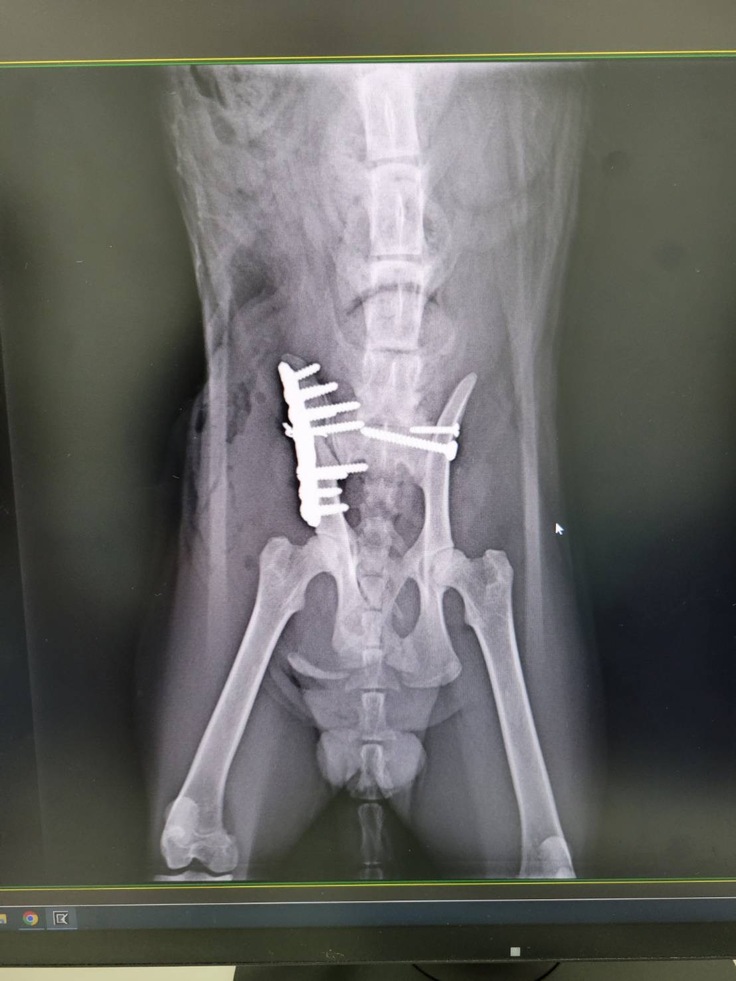

診断名:左仙腸関節脱臼、右腸骨粉砕骨折

両側恥骨と座骨骨折

左仙腸関節脱臼、右腸骨粉砕骨折

両側恥骨と座骨骨折整復

↓手術前の写真

術後のレントゲン写真